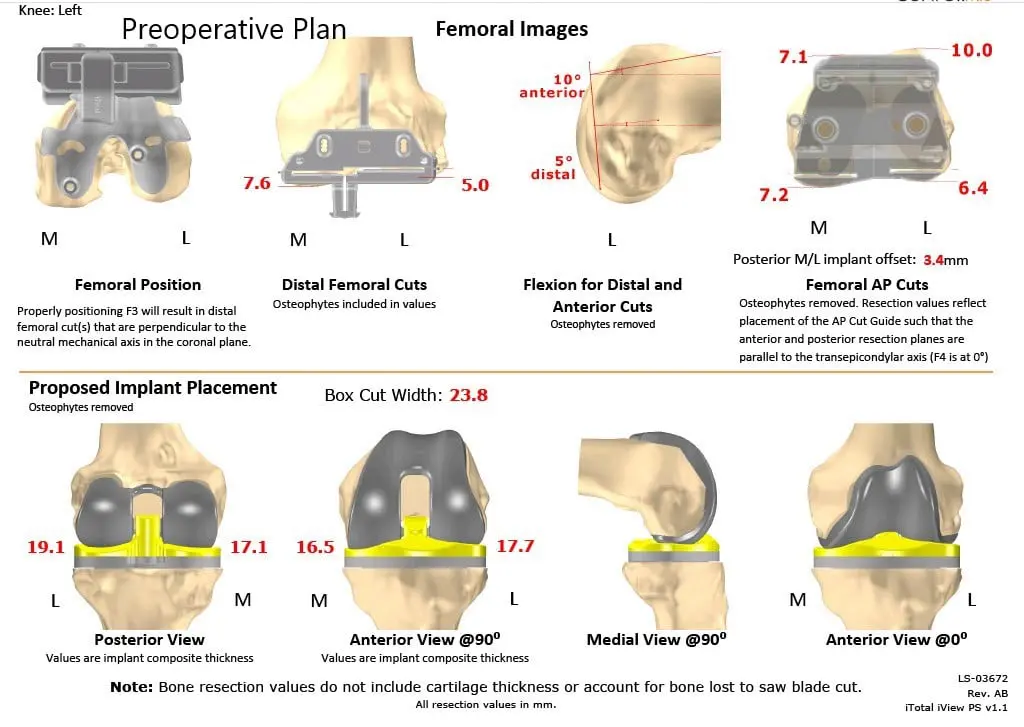

The patient had a preoperative CT scan for assessing his biomechanics and anatomy to aid in bone preserving surgery. The images were used to construct custom patient-specific implants and instruments. Unique 3D printed cutting blocks are used to preserve maximum bone. Preoperative plans are created using the 3D images to ensure correct alignment and prevent implant mismatch which is common with traditional implants.

Complete Orthopedics patient-specific surgical plan for a left custom knee replacement in a 70-year-old female (scan 2)